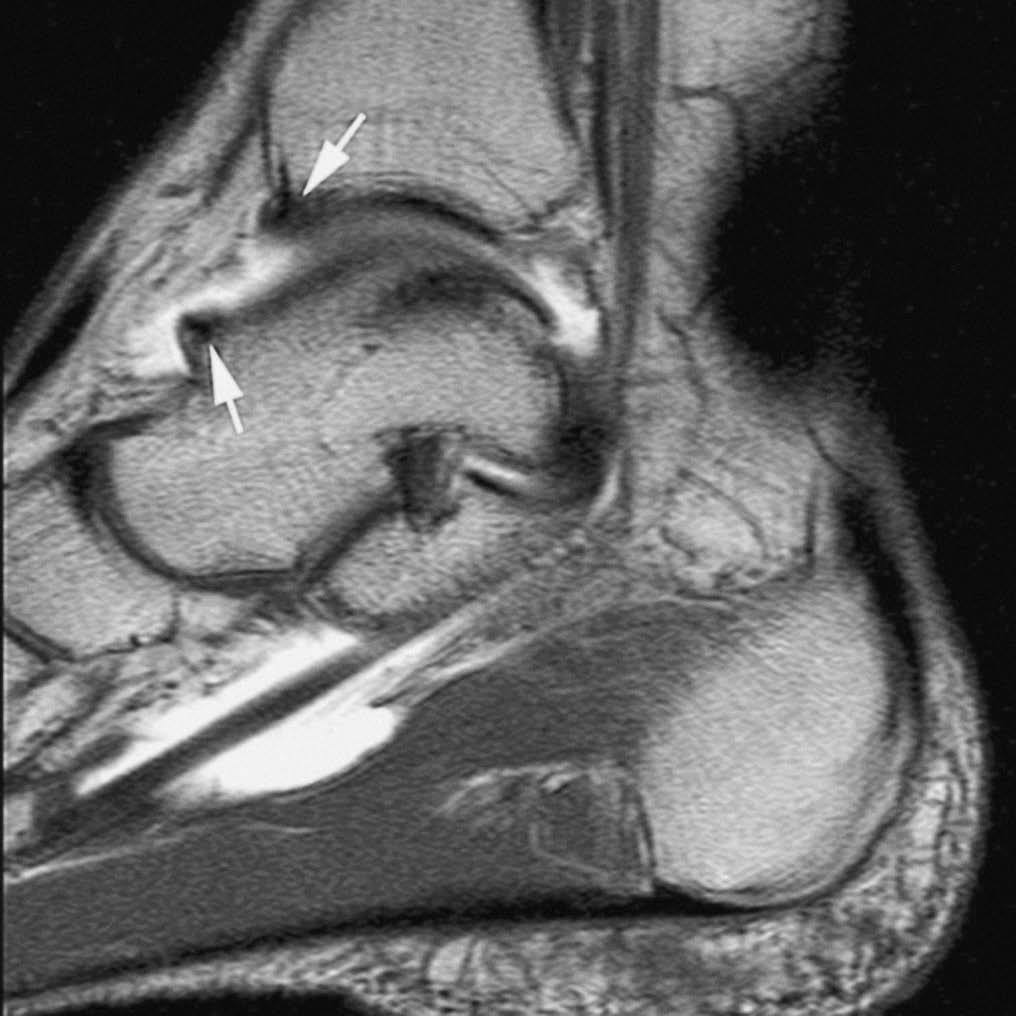

El síndrome de choque anterior es una causa relativamente frecuente de dolor crónico de tobillo, especialmente en deportistas sometidos a estrés repetido del tobillo en dorsiflexión («tobillo de futbolista»). Este proceso produce la existencia de prominencias óseas en el margen anterior del techo tibial, generalmente asociadas a otras en el área correspondiente sobre el margen opuesto del astrágalo. Estos osteofitos pueden chocar entre sí, especialmente con la dorsiflexión del tobillo, y atrapar tejidos de partes blandas. La RMA es de gran utilidad en la valoración de la afectación condral y la sinovitis (fig. 11) en el receso capsular anterior del tobillo19,23.

Fig. 11.--Síndrome de choque anterior. Corte sagital de RMA potenciado en T1 en el que se observan espolones óseos en el reborde tibial anterior y en la vertiente dorsal del cuello del astrágalo (flechas).